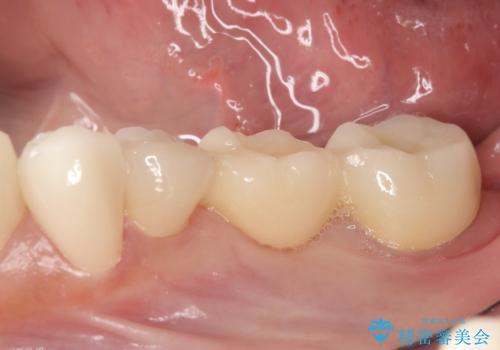

銀歯のブリッジをジルコニアブリッジへ

- 笑った時に大きく見えてしまう奥歯の銀歯ブリッジを白くしたいと希望され来院されました。

強度があり、審美性にも優れるジルコニアブリッジに置き替えていく治療計画としました。

ブリッジに見えない自然な仕上がりに喜んでいただくことができました。